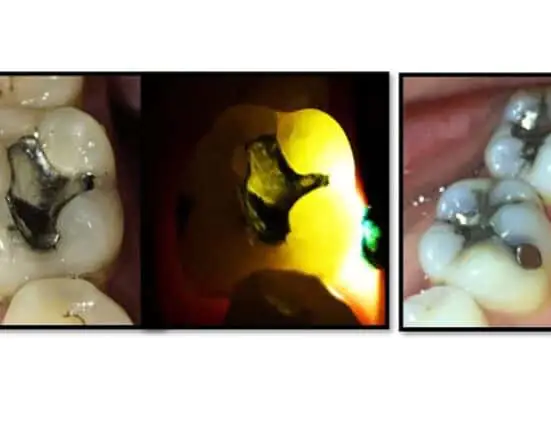

In a prospective study of teeth with deep cracks extending onto the root surface, Davis and Shariff found a success rate of 91% and survival of 97% when employing modern microscopic endodontic technique as well as the aforementioned postoperative management protocols (Figures 4 and 5).

| Figure 5. (A) Cracked tooth No. 3, (B) with the occlusal amalgam removed, (C, D) endodontic treatment complete showing multiple cracks extending well into the MB2, DB, and P canals, and (E) orifice barriers placed. (F, G) Post-operative and 4-year radiographs respectively. |